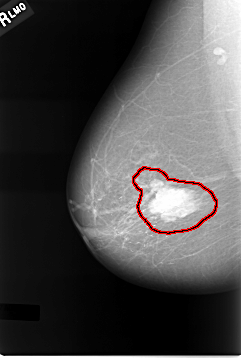

C_0011_1.RIGHT_CC

FILE: C_0011_1.RIGHT_CC.OVERLAY

TOTAL_ABNORMALITIES 1

ABNORMALITY 1

LESION_TYPE MASS SHAPE LOBULATED MARGINS CIRCUMSCRIBED

ASSESSMENT 5

SUBTLETY 5

PATHOLOGY MALIGNANT

TOTAL_OUTLINES 1

BOUNDARY